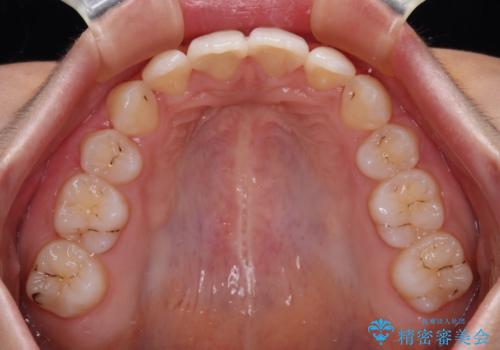

高校生ということもあり、治療期間は2年を切るスピードでした。

舌の突出癖は十分に改善されたとは言えない状態でしたので、今後の後戻り防止対策として、経過観察中も舌のトレーニング指導を行っていくこととなります。